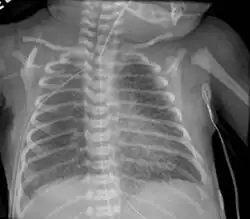

| Micrograph of an emphysematous lung; emphysema is a respiratory disease, strongly associated with smoking. H&E stain. | |

Infant respiratory distress syndrome most commonly occurs in less than six hours after birth in about 1% of all births in the United States.[9] The main risk factor is prematurity with the likelihood of it occurring going up to 71% in infants under 750g.[20] Other risk factors include infant of a diabetic mother (IDM), method of delivery, fetal asphyxia, genetics, prolonged rupture of membranes (PROM), maternal toxemia, chorioamnionitis, and male sex. The widely accepted pathophysiology of respiratory distress syndrome is it caused by insufficient surfactant production and immature lung and vascular development. The lack of surfactant makes the lungs atelectatic causing a ventilation to perfusion mismatch, lowered compliance, and increased air resistance. This causes hypoxia and respiratory acidosis which can lead to pulmonary hypertension. It has a ground glass appearance on an x-ray. Symptoms can include tachypnea, nasal flaring, paradoxical chest movement, grunting, and subcostal retractions.[9]

Pulmonary interstitial emphysema is the condition of air escaping overdistended alveoli into the pulmonary interstitium. It is a rare disease that occurs most often in premature infants, even though it is possible to appear in adults.[26] It often presents as a slow deterioration with the need for increased ventilatory support. Chest x-ray is the standard for diagnosis where it is seen as linear or cystic translucencies extending to the edges of the lungs.[9]